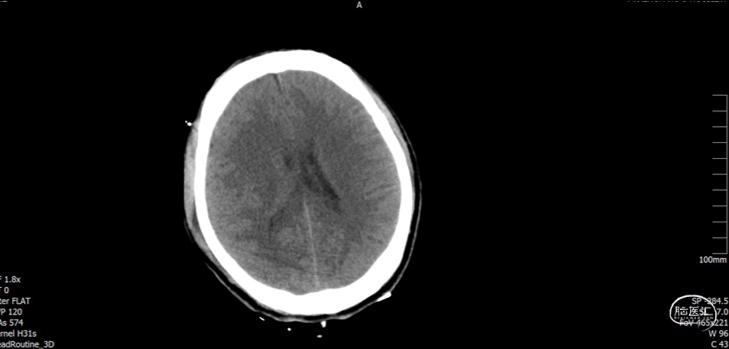

病例资料

男, 34岁。

主诉:高空坠物砸伤头部后左侧肢体活动失灵2小时。

现病史:患者于入院前2小时在工地干活时被高空坠物砸伤头部(具体过程不详),伤后出现左侧肢体活动失灵,被同事送往我院急诊科就诊,入急诊时神志清醒,GCS15分,行颅脑CT提示:1. 右侧颞顶骨骨折,顶骨多发骨折并部分嵌插脑内;2. 右侧顶叶脑挫伤;3. 右侧额颞顶部硬膜下血肿;4. 蛛网膜下腔出血。急诊予以清创、止血及对症治疗。期间患者意识障碍加重呈嗜睡,GCS14分,我科急会诊后以“1. 开放性颅脑损伤特重型 1.1开放性颅内异物1.2脑挫裂伤1.3蛛网膜下腔出血1.4颞顶骨骨折(右);2. 偏瘫(左)”收住入院。自发病来,患者暂无抽搐、晕厥等症状,小便失禁。

入院查体:右顶部头皮见长约2.0cm开放性伤口,出血并脑脊液漏出,颅骨嵌入。神志嗜睡,GCS评分:E3+V5+M6=14分。双侧瞳孔等大正圆,直径均约3.0mm,直、间接对光反射灵敏。左侧上下肢肌力约I/0级,右侧上下肢肌力约IV/IV级。